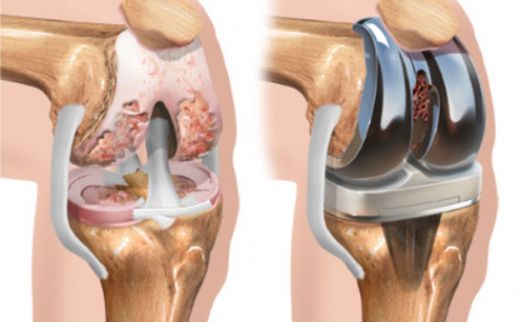

Diz Kıkırdak Belirtileri ve Tedavisi Diz kıkırdağı, diz ekleminin düzgün çalışabilmesi için kritik bir yapı oluşturur. Kıkırdak, eklem yüzeylerini kaplayarak sürtünmeyi azaltır ve hareket sırasında şok emici bir görev üstlenir. Ancak, çeşitli nedenlerden dolayı diz kıkırdağında hasar meydana gelebilir. Bu yazıda, diz kıkırdağında oluşabilecek belirtiler, bu belirtilerin nedenleri ve tedavi yöntemleri detaylı bir şekilde ele alınacaktır. Diz Kıkırdak Hasarının Belirtileri Diz kıkırdağında meydana gelen hasar, çeşitli belirtilerle kendini gösterebilir. Bu belirtiler, hasarın ciddiyetine ve nedenine bağlı olarak değişiklik gösterebilir. Yaygın belirtiler şunlardır:

Diz Kıkırdak Hasarının Tedavi Yöntemleri Diz kıkırdak hasarının tedavisi, hasarın ciddiyetine ve bireyin genel sağlık durumuna bağlı olarak değişir. Tedavi yöntemleri arasında şunlar bulunmaktadır: